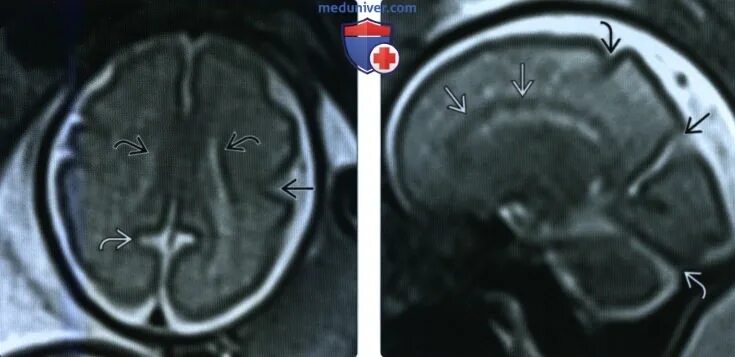

Суб и супратенториальные структуры головного мозга